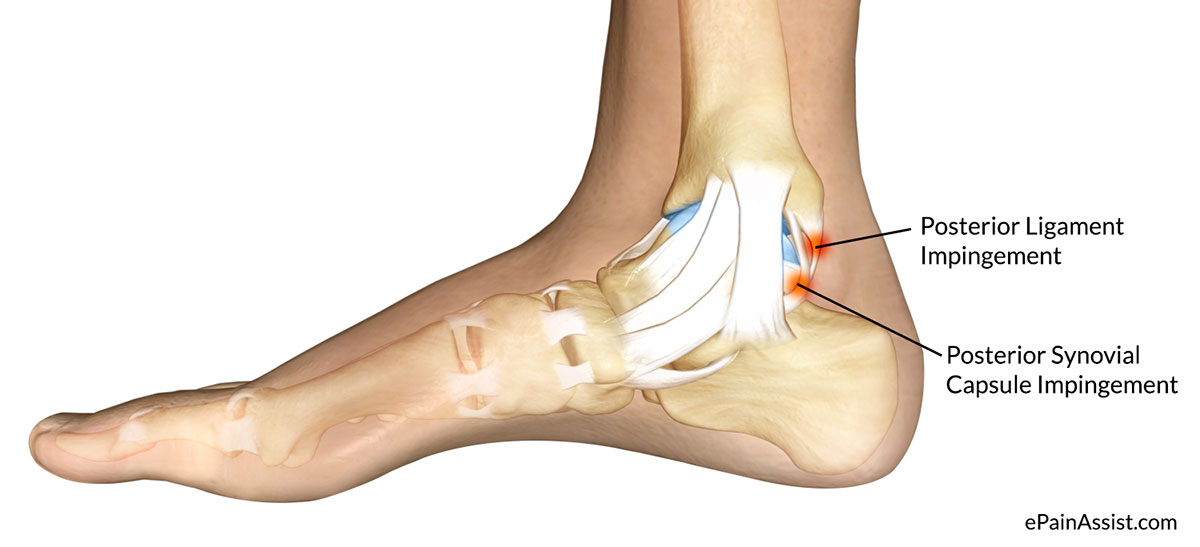

Анатомические фото голеностопного сустава и его суставных поверхностей